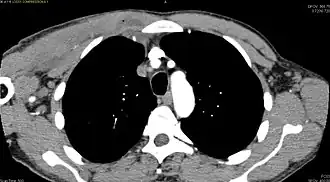

| Diagnostic method | Diagnostic method used for PM includes ultrasound, CT scan and MRI. Ultrasound can be helpful in showing muscular heterogeneity or a purulent collection but it is not useful during the first stage of the disease. CT scan can confirm the diagnosis before abscesses occur with enlargement of the involved muscles and hypodensity when abscess is present, terogenous attenuation and fluid collection with rim enhancement can be found. MRI is useful to assess PM and determine its localization and extension |